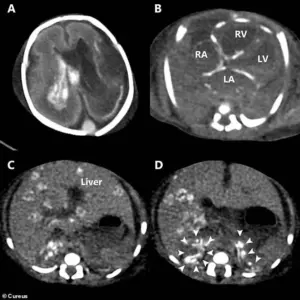

These images from a scan after the baby’s death show how the herpes infection caused catastrophic damage throughout his entire body.

A) Bleeding inside the brain’s fluid-filled chambers (ventricles).

One chamber is also enlarged.

B) Abnormal, dense spots (calcifications) are visible in the walls of the heart’s chambers.

C) Widespread, round, dense spots throughout the liver, indicating tissue damage. (D) Heavy, dense areas in both of the small adrenal glands (located on top of the kidneys), showing they were also severely affected.

A post-mortem CT scan provided the final confirmation of the infection’s destructive path.

The post-mortem CT scan revealed multiple areas of overload of calcium in his tissue, a sign of severe, chronic inflammation, throughout the walls of his heart, liver and adrenal glands.

There was bleeding into the fluid-filled spaces, ventricles, within his brain.

Specifically, the case report noted the bleeding due to its inability to clot was in the left lateral and third ventricles, confirming a disseminated HSV infection that began in the womb.